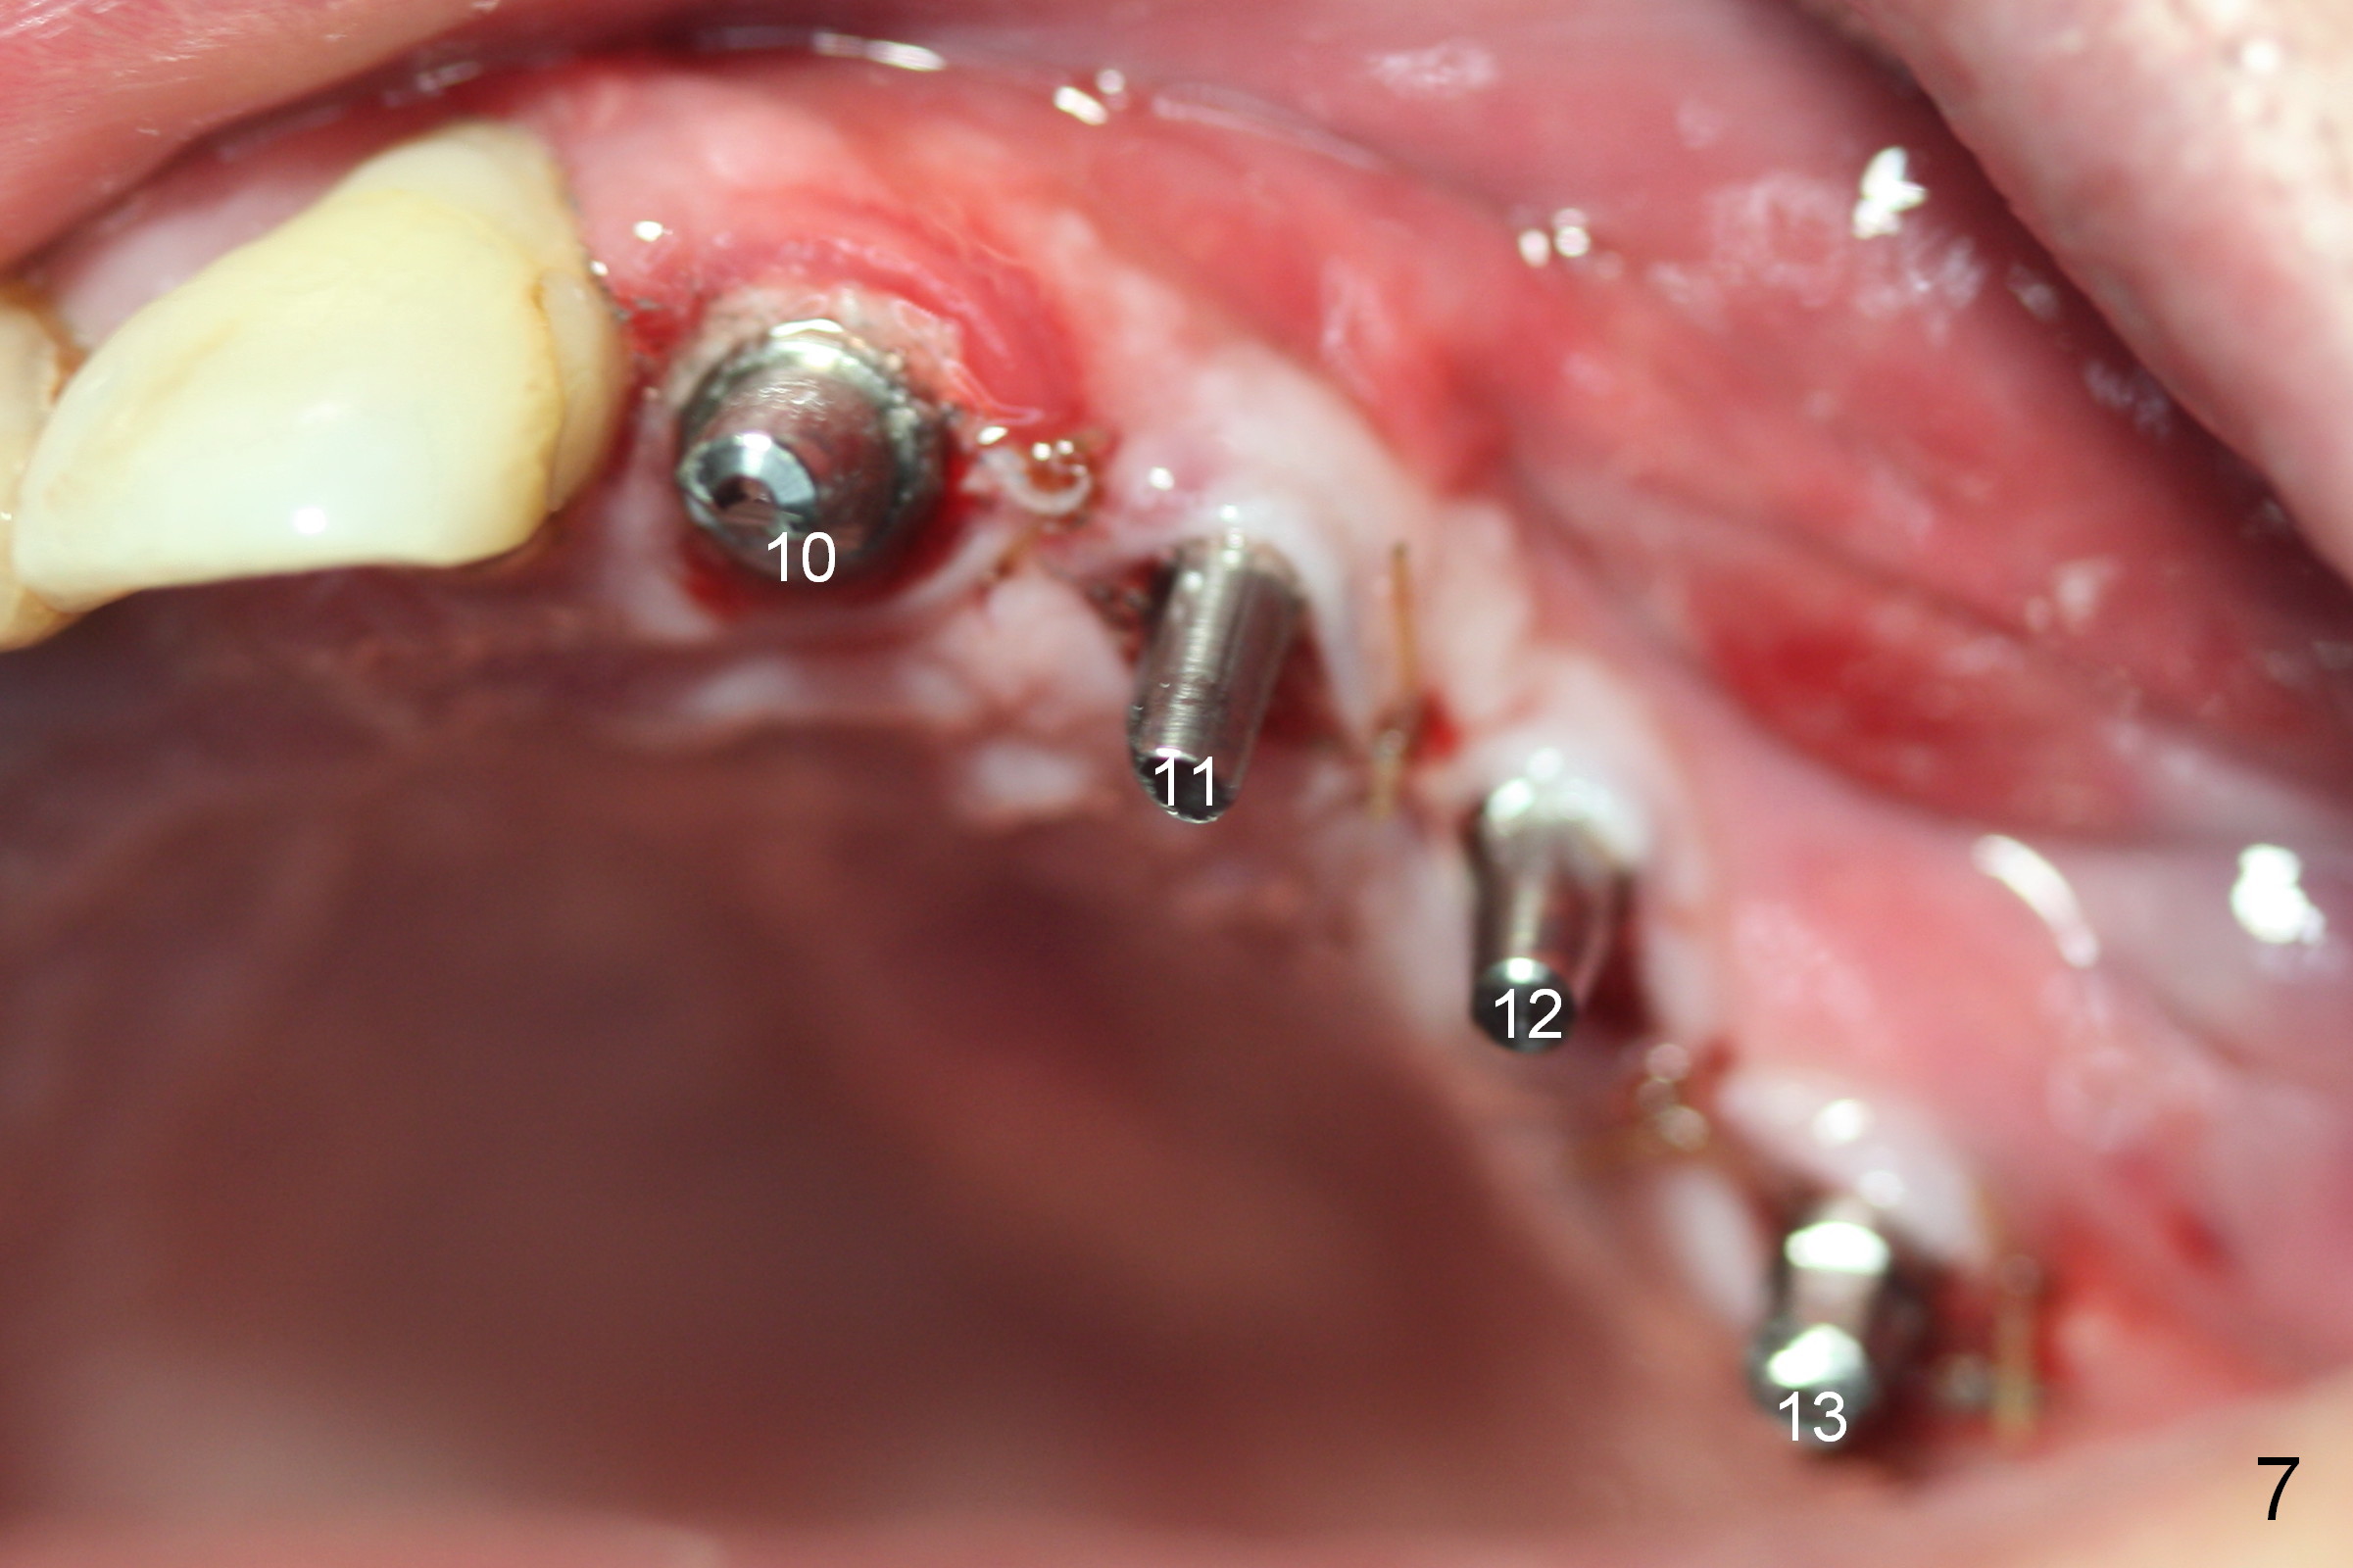

When the patient returns for implant placement (2nd visit after initial exam), he reveals that he is a dental phobic.  He requests placement of 4 implants in the upper left quadrant, instead of 2.  Narrow ridge is unexpected in the canine and premolar area (Fig.1).  Limited bone height at #13 (Fig.3 arrowheads: sinus floor) is found when initial drills are in place (Fig.2,3).  A 2-piece implant (4.5x17 mm tissue-level) is placed at #10 after extraction, while 1-piece implants are placed at 11 (3x17 mm (tissue-level, 15 °) and 12 and 13 (bone-level, 2.5x14, 12 mm, respectively; Fig.4,5).  In fact the 1 piece implant at #13 is not completely placed (Fig.5).  It is removed, the apical 3 threads are cut off (Fig.6 <, since a shorter implant was unavailable in the office) and the remaining implant is re-inserted.  The insertion torques of the 4 implants are ~ 60, ~ 35, < 35 and 15 Ncm, respectively.  After adjustment (Fig.7), immediate provisionals are fabricated at #10 and 11 (Fig.8, later splinted with composite), while perio dressing is applied around the implants at #12 and 13 and the provisionals at #10 and 11.  There is no nasal hemorrhage postop.  Although the perio dressing is loose 1 week postop (Fig.9), it is not removed.  When the upper lip fissure (Fig.9 <) heals, provisionals at #12 and 13 are planned to be splinted to the other two ones.  Two weeks postop, the upper lip fissure heals, the perio dressing dislodges and the implants at #12 and 13 are stable (Fig.10).  After abutment height adjustment, a splinted provisional is fabricated over these 2.5 mm 1-piece implants (Fig.11).